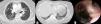

Of the 29 patients diagnosed with BAF in 1 unit, 3 females had an associated diagnosis of ILD. Two patients had a UIP pattern,5 while the third had an NSIP pattern. Both patients were elderly females, never smokers, with a significant history of biomass fuel smoke exposure. Chest high resolution computed tomography (HRCT) in the first patient revealed interlobular septal thickening with ground glass opacities and traction bronchiectasis in a sub-pleural distribution suggestive of fibrotic NSIP pattern, along with multifocal narrowing of right upper lobe bronchus (Fig. 1A). Interlobular septal thickening along with honeycombing in a basilar and sub-pleural distribution suggestive of UIP pattern was seen in the second patient (Fig. 1B). Both patients desaturated on 6-minute-walk test, while pulmonary function testing revealed a restrictive defect. FOB showed anthracotic pigmentation and narrowing/distortion of the affected bronchi (Fig. 1C). Transbronchial biopsy in the first patient suggested NSIP, while it was inconclusive in the other. Stains and cultures of bronchial aspirate were negative.

(A) High resolution computed tomography (HRCT) of the thorax [lung window] showing interlobular septal thickening along with ground glass opacities and traction bronchiectasis in a sub-pleural distribution with multifocal narrowing of the right upper lobe bronchus (white arrow). (B) Chest high resolution computed tomography (HRCT) (lung window) showing interlobular septal thickening along with honeycombing in a basilar and sub-pleural distribution suggestive of UIP pattern. (C) Fiberbronchoscopic image showing anthracotic pigmentation of bronchial mucosa with narrowing and distortion of the apical segment of right upper lobe bronchus.